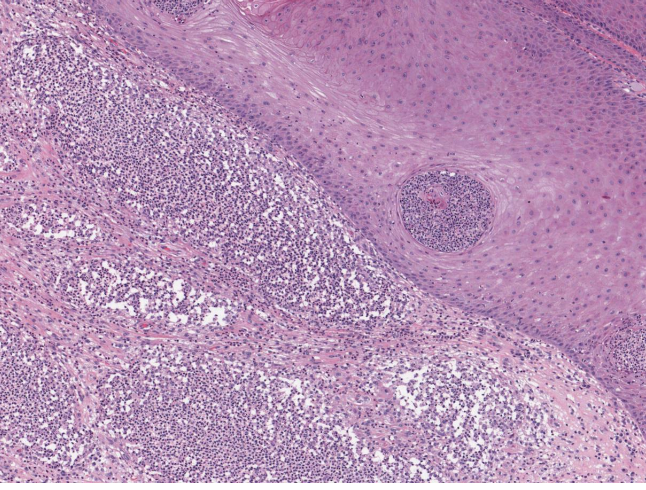

what abnormal process is happening here?

necrosis